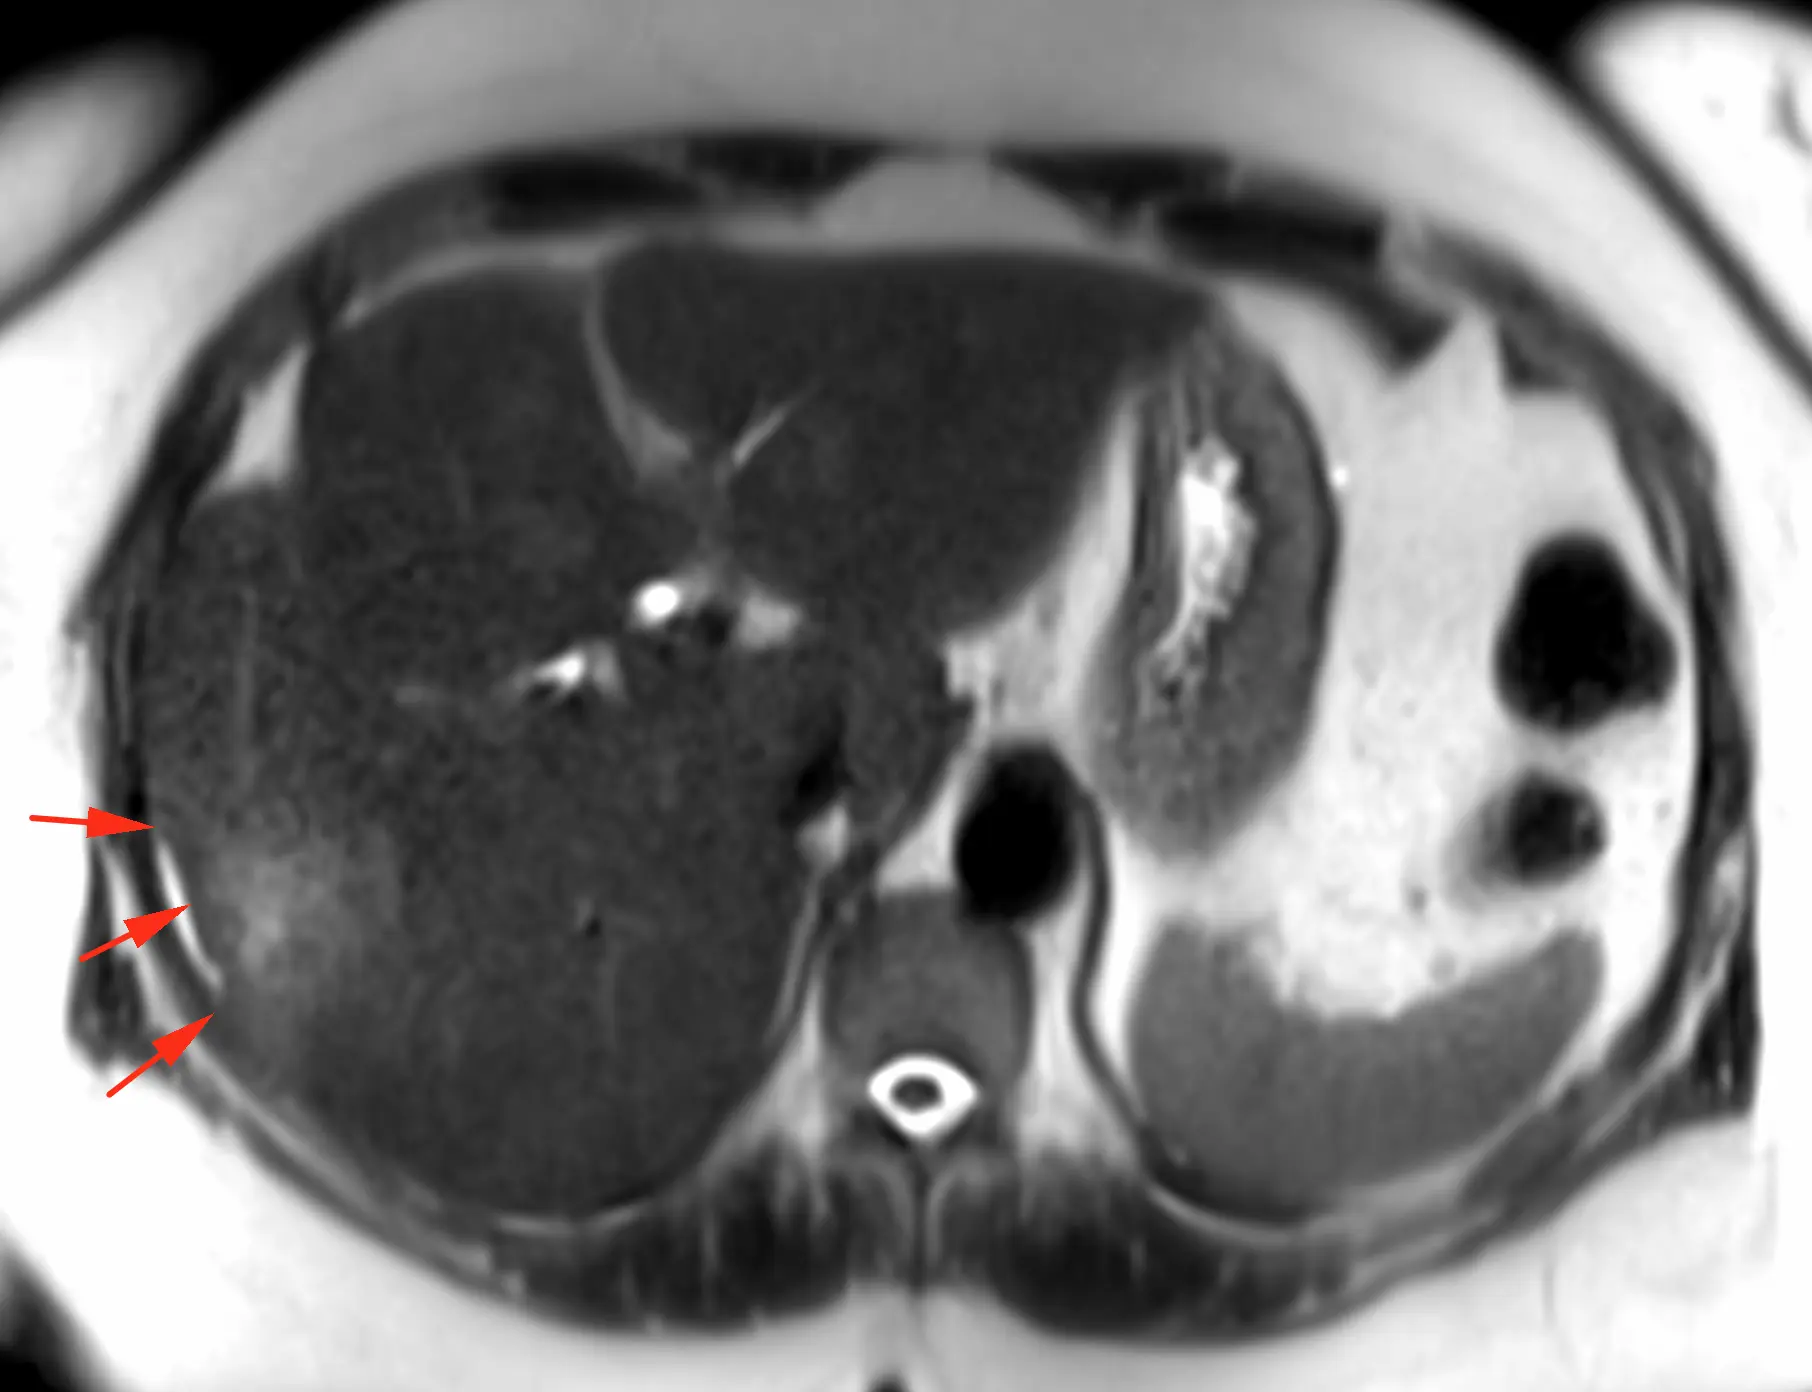

Хороший пример (не верифицирован, но все же, уж больно характерный вид) дифференциальной диагностики множественных новообразований печени. Пациент 63 года. Морфология кольцевидная и на контрастом усиленных сканах, и на диффузии, но не идеально шаровидная, солидный край толстый и неравномерной толщины, артериального гиперконтрастирования больше, чем у паренхимы печени нет (что против гепатоцеллюллярного рака), вымывания нет (тоже против ГЦР), накопление в центре постепенное и медленное. Голосую за периферическую холангиокарциному (или первично множественную, или с внутрипечёночной диссеминацией). А ещё за холангиокарциному - ретракция контура печени и расширение протоков мелких вверх по течению: это достаточно специфично именно для холангиокарциномы. Для гиперваскулярных метастазов нехарактерно отсутствие гиперваскулярности (нет быстрого накопления с вымыванием), на гиповаскулярные, в принципе, паттерн контрастирования, похож, но не похожа морфология (не шарики, не идеальные колечки, ретракция печени, расширение протоков вверх по течению - не характерны для метастазов). Посмотрим, угадаем ли. Но случай интересный. Показательный.